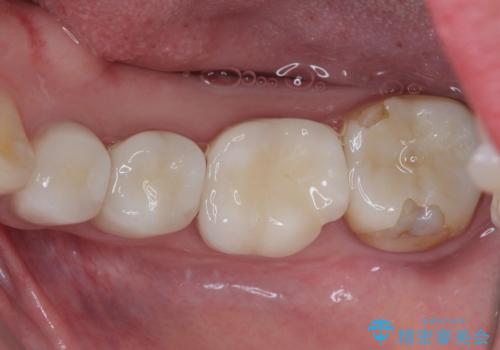

痛みが引いた後、不揃いな見た目で気になっていた左下の奥歯とともにオールセラミッククラウンにて補綴治療を行うこととしました。

右上の歯は、第二小臼歯の初回処置後に痛みを感じなくなったため、他の歯については問題なしと診断しました。

将来ホワイトニングをされるとのことで、前歯よりもやや白い色合いのオールセラミッククラウンを選択されました。